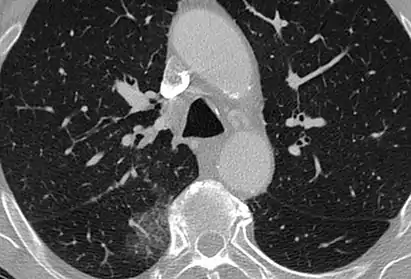

CT showing diffuse ground-glass opacities in periphery of both lungs in patient with COVID-19.

Ground-glass opacity is among the most common imaging findings in patients with confirmed COVID-19.[16][17] One systematic review found that among patients with COVID-19 and abnormal lung findings on CT, greater than 80% had GGOs, with greater than 50% having mixed GGOs and consolidation.[16] GGOs with mixed consolidation has most often been found in elderly populations.[18] Several studies have described a pattern among initial, intermediate, and hospital discharge imaging findings in the disease course of COVID-19. Most commonly, initial CT imaging reveals bilateral GGOs at the periphery of the lungs. During initial stages, this is most often found in the lower lobes, although involvement of the upper lobes and right middle lobe has also been reported early in the disease course.[16][18] This is in contrast to the two similar coronaviruses, SARS and MERS, which more commonly involve only one lung on initial imaging.[19][20] As the COVID-19 infection progresses, GGOs typically become more diffuse and often progress to consolidation.[11][18] This is sometimes accompanied by the development of a crazy paving pattern and interlobular septal thickening.[18] In many cases the most severe pulmonary CT abnormalities occurred within 2 weeks after symptoms began.[17] At this point, many individuals begin showing resolution of consolidation and GGOs as symptoms improve. However, some patients have worsening symptoms and imaging findings, with further increase in septal thickening, GGOs, and consolidation. These patients may develop lung "white-out" with progression to acute respiratory distress syndrome (ARDS) requiring treatment escalation.[17][21]